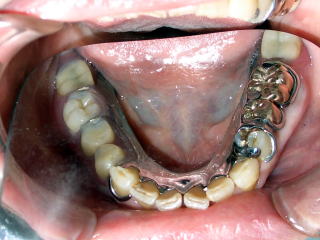

<金属のプレートの入れ歯を使えば

歯周病で弱った歯を護れます> |

取り外し式の入れ歯は手入れが面倒で歯に悪いものと思っていませんか?

金具と一体型の薄い金属の板でできたメタルプレート義歯は、装着時の違和感が少なく、歯周病でぐらぐらになった弱った歯を固定して護る効果があります。

コルセットのような装具ですので、ご興味のある方は一度ご相談ください。 |

| メタルプレート義歯の写真 |